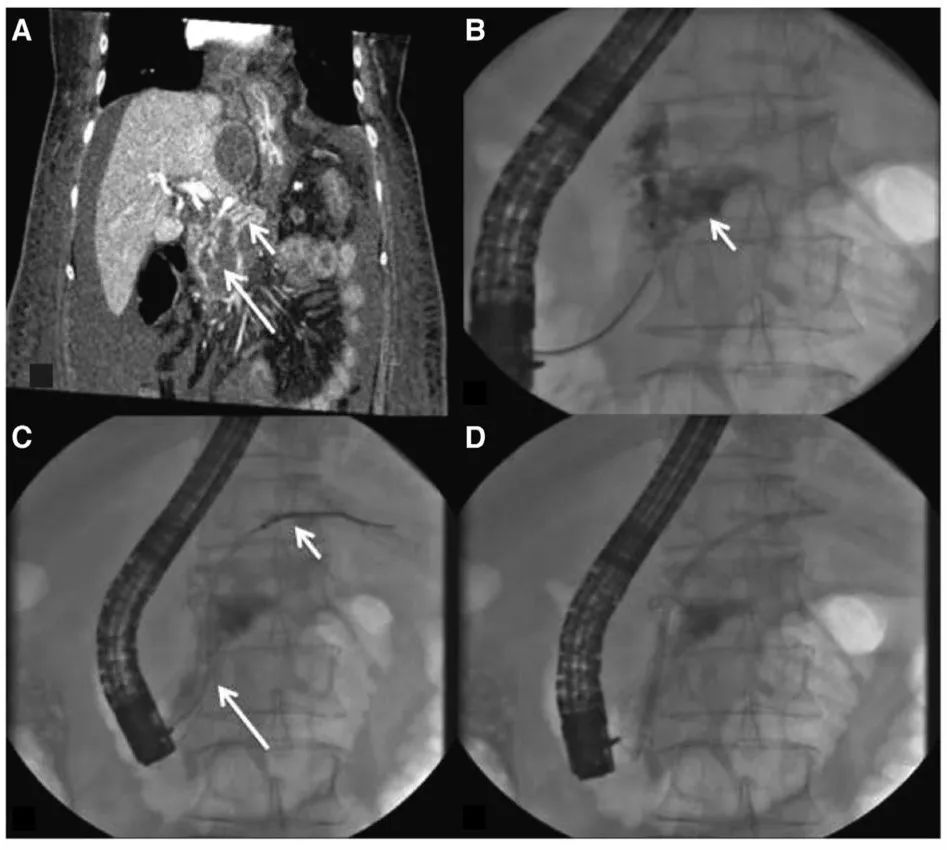

除了传统的手术方式,现在值得尝试的一种方式为经乳头放置胰管支架,使用支架对两个断端进行“桥接”(图6),另一种方式为跨壁引流,具体的做法是放置双猪尾支架,将囊液引流至胃肠道,但是支持这些做法的相关研究质量并不高。

图6 经乳头放置胰管支架